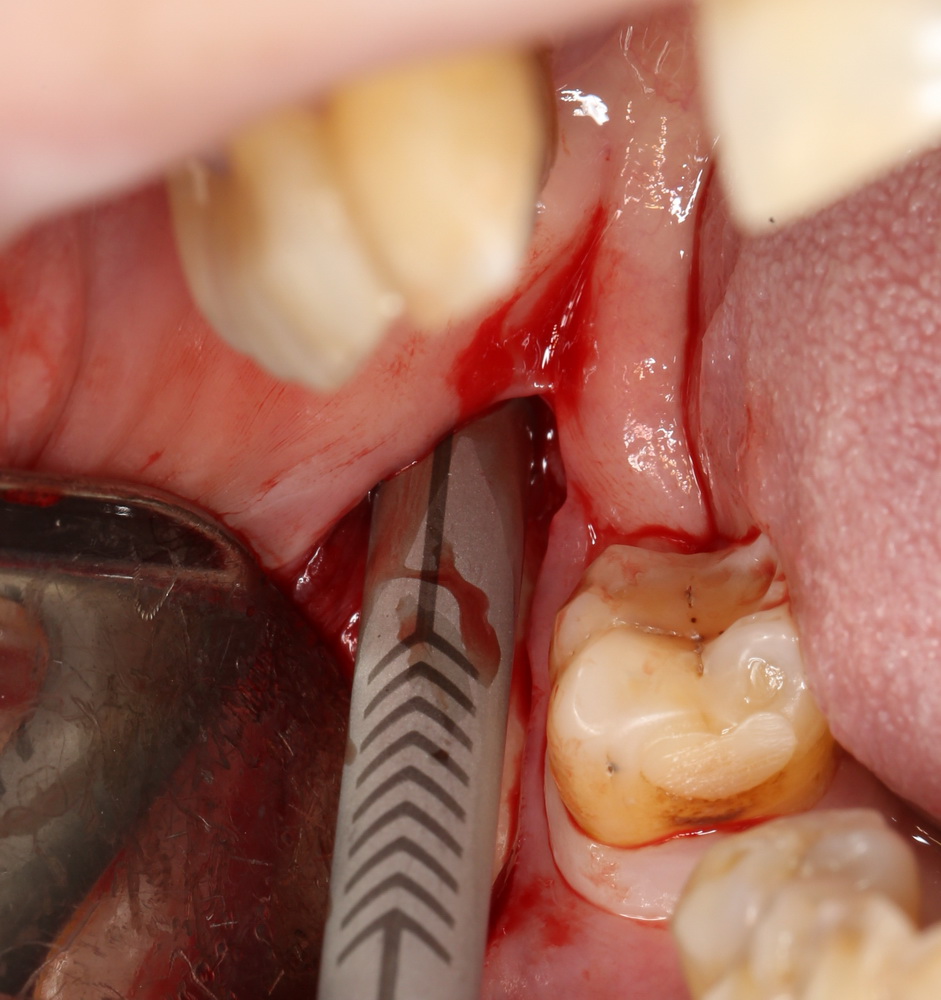

Что же касается нерезорбируемых мембран… Было дело, работал с Gore-Tex (дорого, очень дорого), титановыми сетками (заколебался потом доставать) и тефлоновыми Cytoplast:

результат:

или

с трудом выковыриваем сетку и ищем имплантат:

чтобы поставить формирователь: